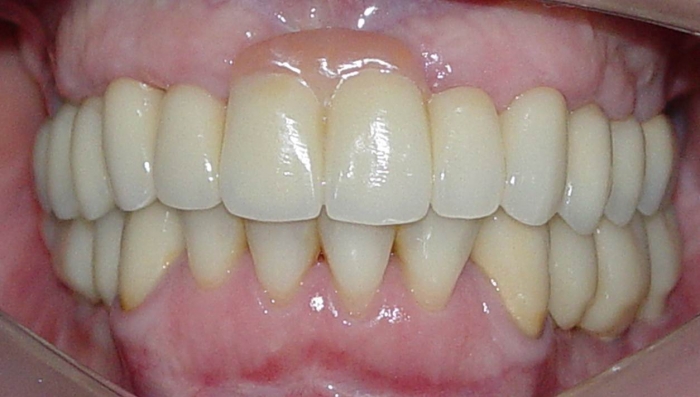

Imagens da prótese fixa superior em porcelana sobre implantes Cone Morse

Sorriso final do caso terminado em março de 2012